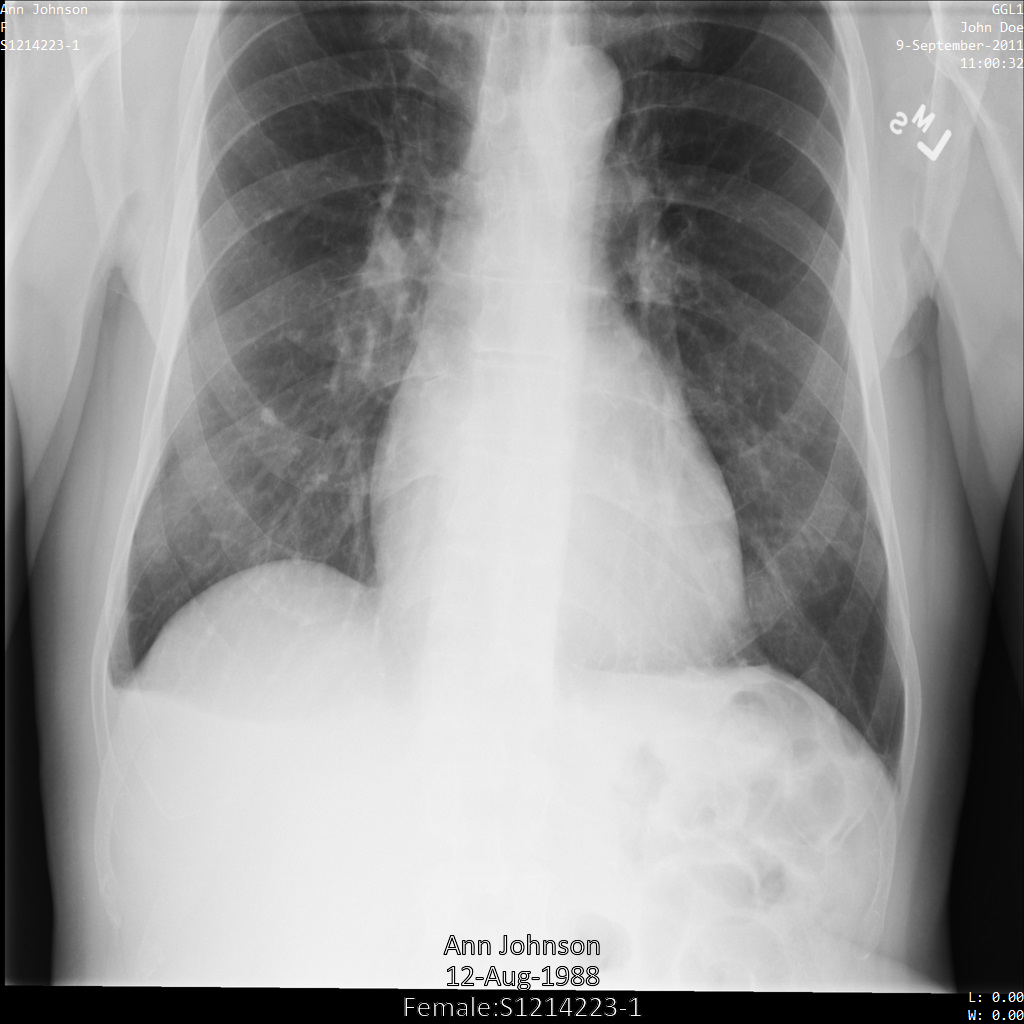

将图片提交到 Cloud Healthcare API 后,图片显示如下。虽然图片顶部角落显示的元数据已被遮盖,但图片底部的烧屏受保护健康信息 (PHI) 仍然保留。如需一并移除烧屏文字,请参阅遮盖图片中的烧屏文字

dicom_keeplist